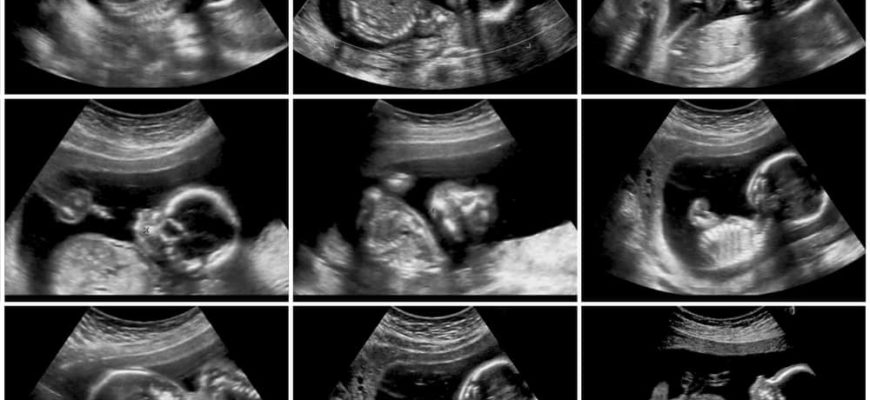

Ультразвуковое исследование (УЗИ) стало одним из основных методов диагностики во многих областях практической медицины благодаря большому объему информации, доступности, простоте выполнения и отсутствию неблагоприятного воздействия на организм человека. В акушерстве он, вероятно, приобрел наибольшее значение по сравнению со всеми другими методами, поскольку оказался наиболее надежным при оценке развития будущего ребенка и течения беременности, особенно при нарушениях беременности.

Согласно Приказу Минздрава России от 1 ноября 2012 года ультразвуковое обследование проводится 3 раза по месту регистрации женщины в следующие даты: 11-14 (I триместр), 18-21 ( второй триместр) и 30-34 (третий триместр) неделя беременности.

При необходимости повторные осмотры могут быть назначены на другие даты. Во время наблюдения в пренатальной клинике отслеживается состояние плода и динамика его развития, выявляются наиболее частые и поздно выявляющиеся генетические аномалии, как можно раньше диагностируется риск развития плацентарной недостаточности. Плановое УЗИ при беременности позволяет получить достаточно достоверную и объективную информацию.